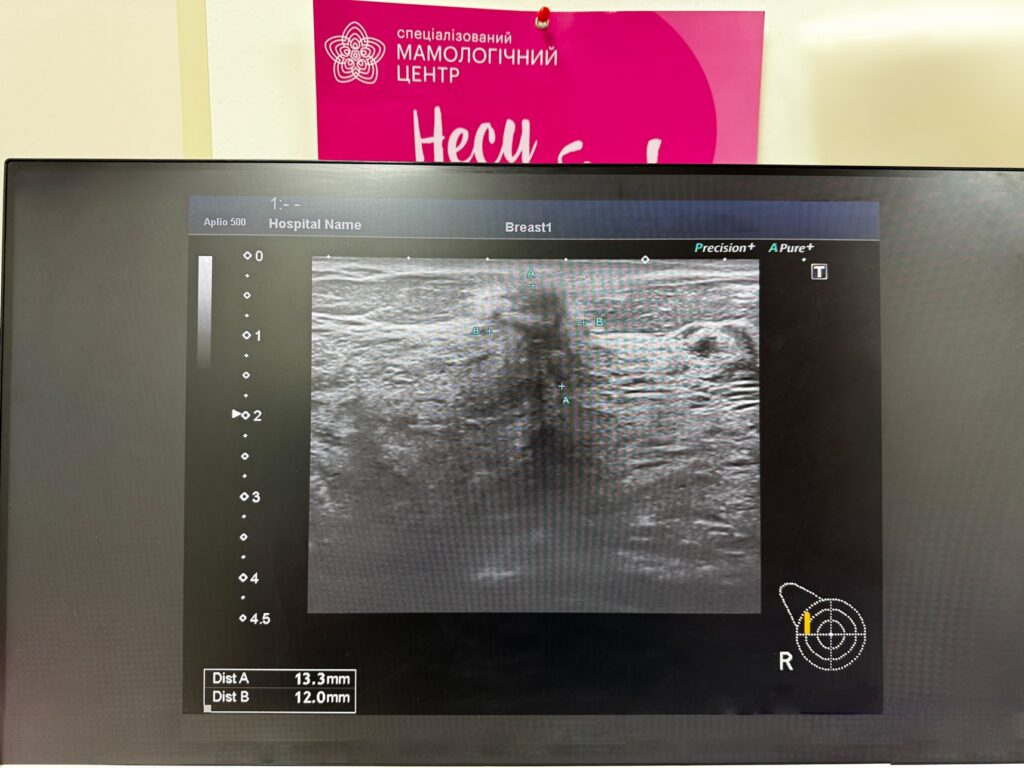

- УЗД молочної залози – сканування ультразвуковими хвилями. Як виглядає рак молочної залози на УЗД – можна побачити на фото.

Це зазвичай об’ємне утворення з нечіткими контурами, що має вертикальний розмір більший, ніж горизонтальний. Додаткові режими ультразвукового дослідження – еластографія та доплерографія – підвищують шанси на виявлення злоякісного процесу, у тому числі й тих пухлин, які погано візуалізуються (патологічно змінені ділянки мають особливості кровоплину та інші показники пружності). - Мамографія – рентгенографічне дослідження. Дозволяє виявити новоутворення та інші ознаки патологічного процесу (наприклад, кальцинати у молочній залозі). Для отримання найточніших результатів можуть проводитися такі види досліджень, як контрастна мамографія, мамографія з томосинтезом.